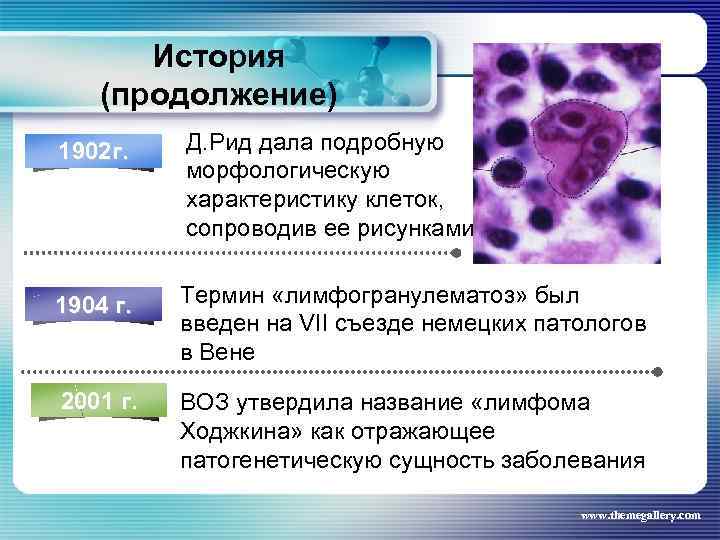

История (продолжение) 1902 г. Д. Рид дала подробную морфологическую характеристику клеток, сопроводив ее рисунками 1904 г. Термин «лимфогранулематоз» был введен на VII съезде немецких патологов в Вене 2001 г. ВОЗ утвердила название «лимфома Ходжкина» как отражающее патогенетическую сущность заболевания www. themegallery. com

История (продолжение) 1902 г. Д. Рид дала подробную морфологическую характеристику клеток, сопроводив ее рисунками 1904 г. Термин «лимфогранулематоз» был введен на VII съезде немецких патологов в Вене 2001 г. ВОЗ утвердила название «лимфома Ходжкина» как отражающее патогенетическую сущность заболевания www. themegallery. com